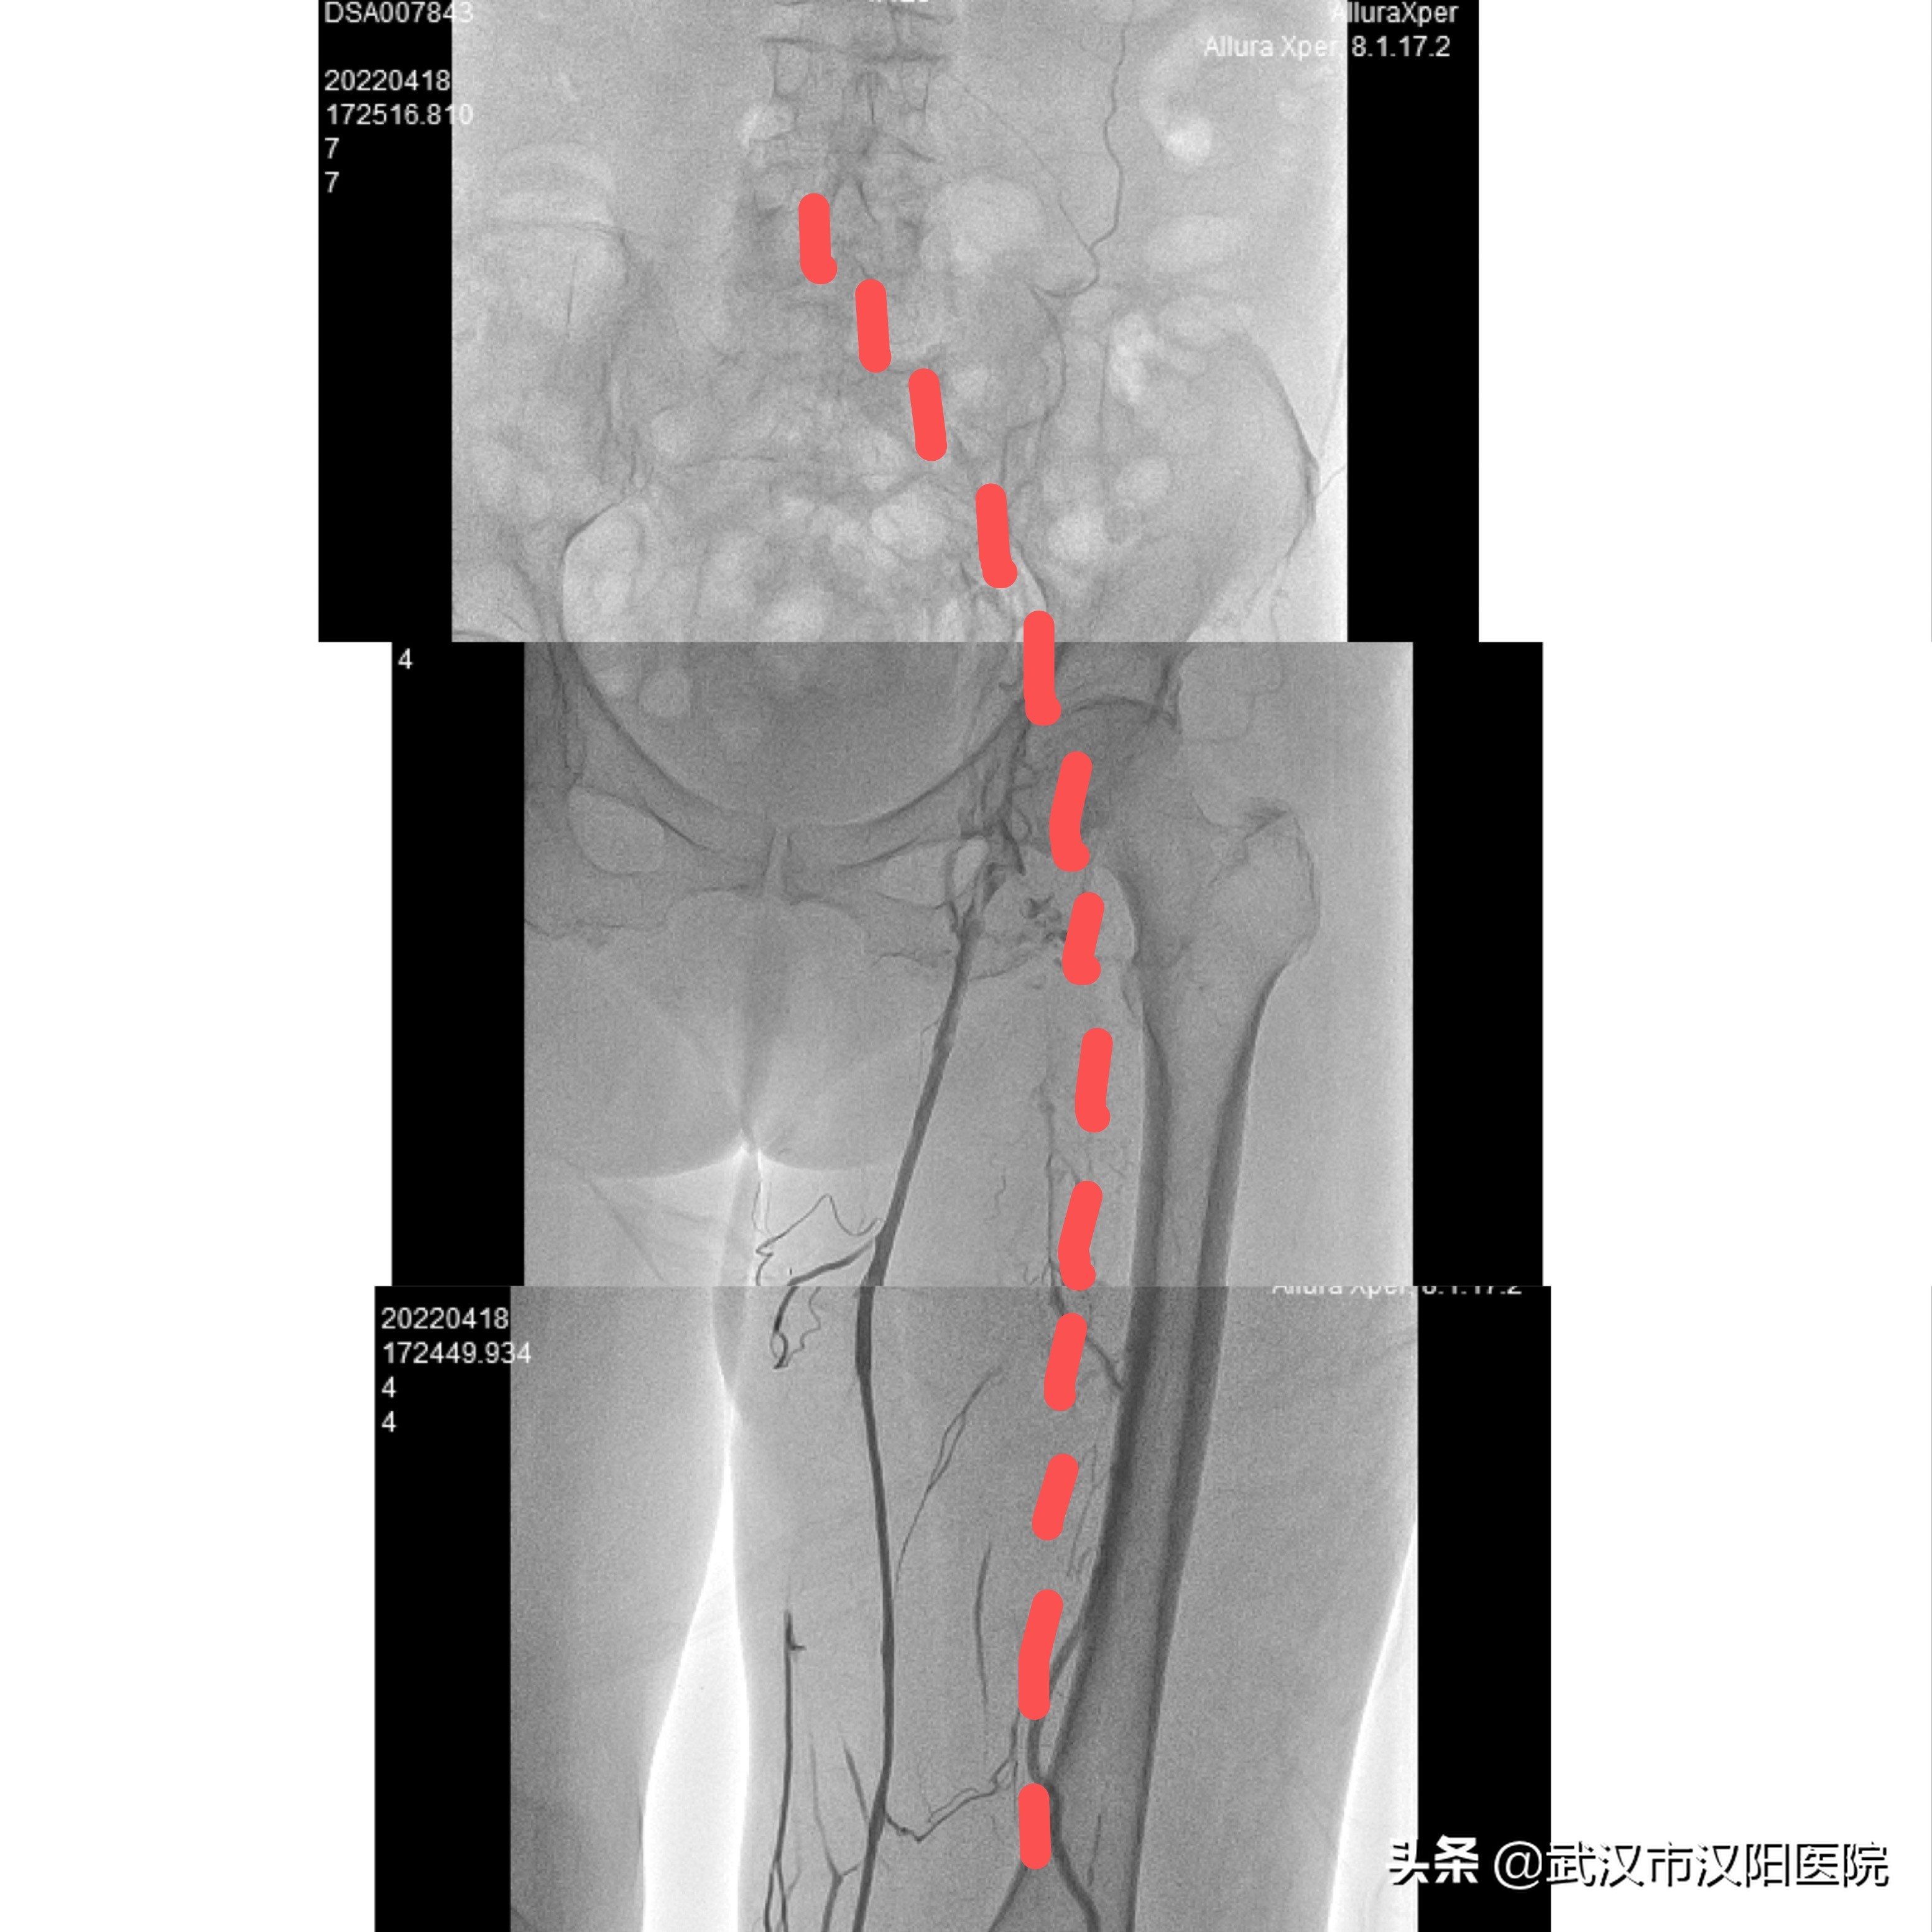

图1:经足背静脉造影,深静脉髂股腘静脉均未显影

血管外科赵红主任查看后,发现她的两侧大腿的腿围相差近8cm,经足背静脉造影发现,她的左下肢髂股腘静脉弥漫性血栓形成,血栓负荷量极大,且有存在左髂静脉重度狭窄可能,左下肢需要进一步处理。经与其家属初步沟通后,选择先做抗凝保守治疗。观察一周后发现,当老人家卧床时症状得到改善,但离床活动后,左下肢还是出现明显的肿胀。

图2:抗凝一周后股腘静脉显影,髂静脉未显影